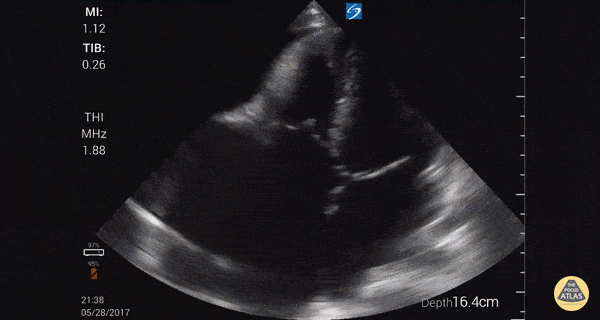

Young male from Latin America with findings of right HF. Focused cardiac ultrasound shows massive RA, moderate pericardial effusion, relatively normal RV and LV. Significant TR ruled out. Findings consistent with Endomyocardial Fibrosis, found in tropical countries. Need cardiac MRI to confirm. Similar to eosinophilic myocardial fibrosis found in temperate climates. Dr. Gordon Johnson MD Internist Portland Oregon & Uganda SonoPortlandia.com